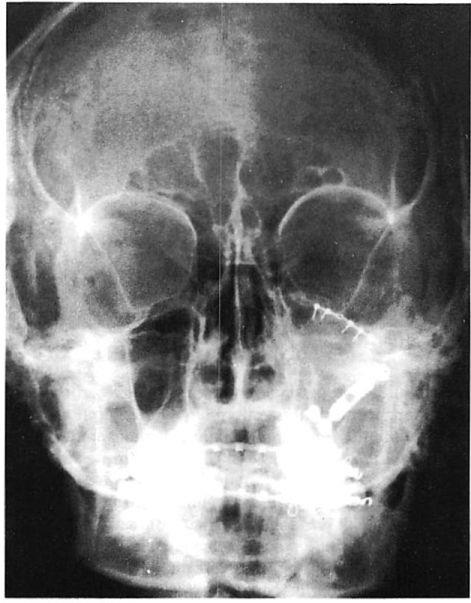

Fig 5. Low-energy zygoma fracture treated with mini- and microfixation. (A) Preoperative axial computed tomographic (CT) scan shows malar displacement. (B) Preoperative coronal CT scan shows slight displacement at zygomaticomaxillary buttress and no displacement at zygomaticofrontal articulation. (C) Postoperative plain film shows miniplate fixation at zygomaticomaxillary buttress and microplate fixation at the infraorbital rim. (Arch bars were used for maxillomandibular fixation to treat associated subcondylar fracture.)

Fig 6. Middle-energy zygoma fracture treated with miniarid microfixation. (A) Preoperative axial computed tomographic (CT) scan shoivs malar displacement and buckling of lateral orbital wall. (B) Preoperative coronal CT scan shows comminution at zygomaticomaxillary buttress and displacement at zygomaticofrontal articulation. There is slight bowing of the zygomatic arch. (C) Postoperative plain film shows microplate at zygomaticofrontal suture area and rim with miniplate at the zygomaticomaxillary buttress. Surgery was performed through a subciliary and gingivobuccal sulcus incision. The arch shape was restored with external pressure.